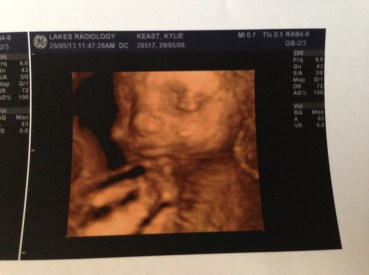

By now I was around 28 weeks pregnant and beginning to plan a baby shower for around 32 weeks, I also had a 3D scan on my 25th birthday which showed us some amazing images and video of Izaac in the womb, just incredible footage and photos that I hold very close to my heart.